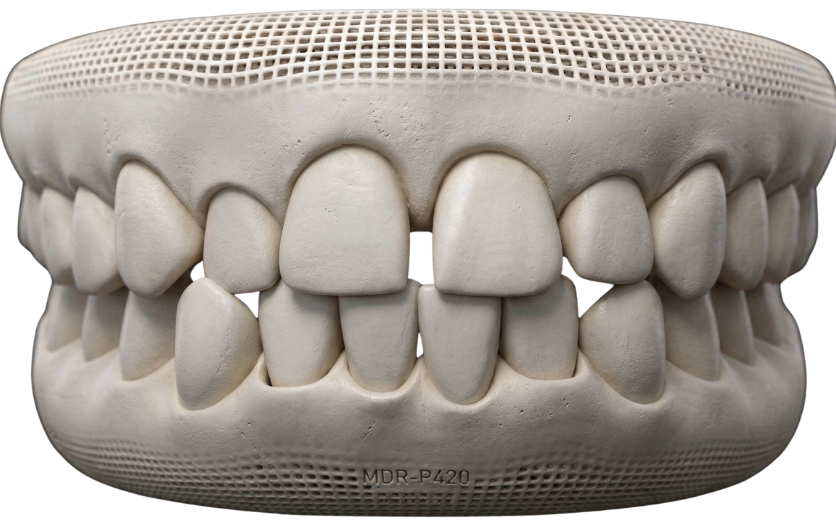

Pediatic Dentistry

Best Pediatric dentistry at The Smile Company is focused on providing gentle, specialized dental care for children in a safe, friendly, and comfortable environment. From early check-ups to preventive and restorative treatments, we ensure your child’s oral health is well taken care of at every stage of growth. Our approach combines clinical expertise with a calm and reassuring atmosphere, helping children feel relaxed and confident during their dental visits. We don’t just treat teeth—we build positive dental experiences that last a lifetime. With patience, care, and a child-friendly approach, we help reduce anxiety and encourage healthy habits early on, so your child grows up with a strong, confident smile.

Need for Pediatric Dentistry?

Cavities & Tooth Decay

Growth & Development Monitoring

Your Child’s Dental Journey

Initial Consultation & Assessment